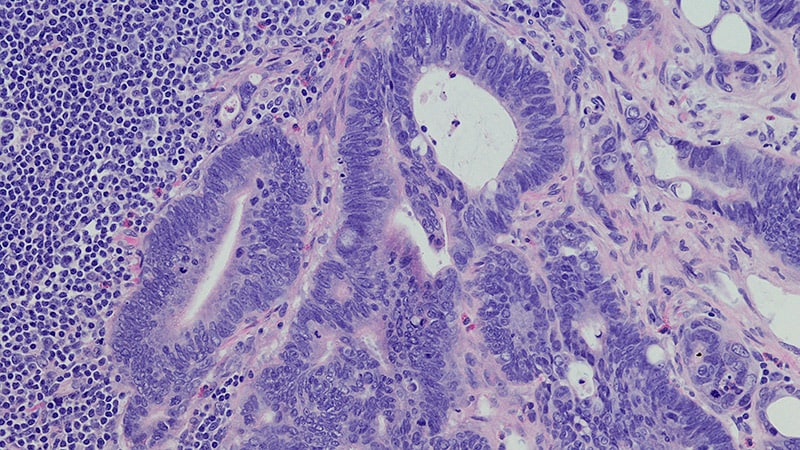

The US Food and Drug Administration (FDA) has approved sotorasib (Lumakras, Amgen Inc.) with panitumumab (Vectibix, Amgen Inc.) for the treatment of certain adult patients with metastatic colorectal cancer (mCRC). Specifically, the combination therapy is indicated for those with KRAS G12C-mutated mCRC, as determined using an FDA-approved test…